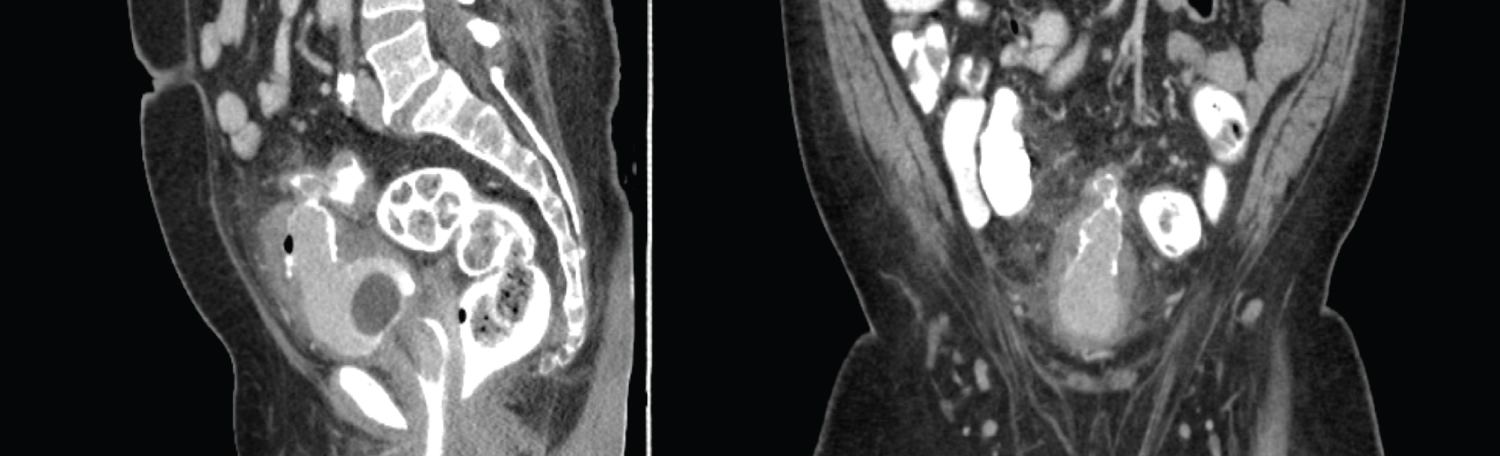

The patient, a 71-year-old male with a history of Benign Prostatic Hyperplasia (BPH), presented with hematuria persisting for two months, which intensified to gross hematuria over the last three days. He also reported dysuria with clots, mostly appearing at the end of urination. Despite being diagnosed with BPH six years ago, the patient irregularly used medication due to irritative and storage symptoms. He denied experiencing vomiting, nausea, fever, night sweats, weight loss, changes in appetite, or alterations in bowel habits. Upon clinical examination, a CT scan revealed diffuse irregular thickening of the urinary bladder wall (up to 1.8 cm) with a partially exophytic mass at the bladder dome (Figure 1). This mass exhibited mucosal breakthrough and was inseparable from the adjacent sigmoid loop, accompanied by mild peri nephric fat stranding. No ureteric filling defects or hydroureteronephrosis were observed.

Figure 1: Coronal and sagital sections of CT pelvis showing Urinary bladder dome partially exophytic mass inseparable from the adjacent sigmoid. View Figure 1